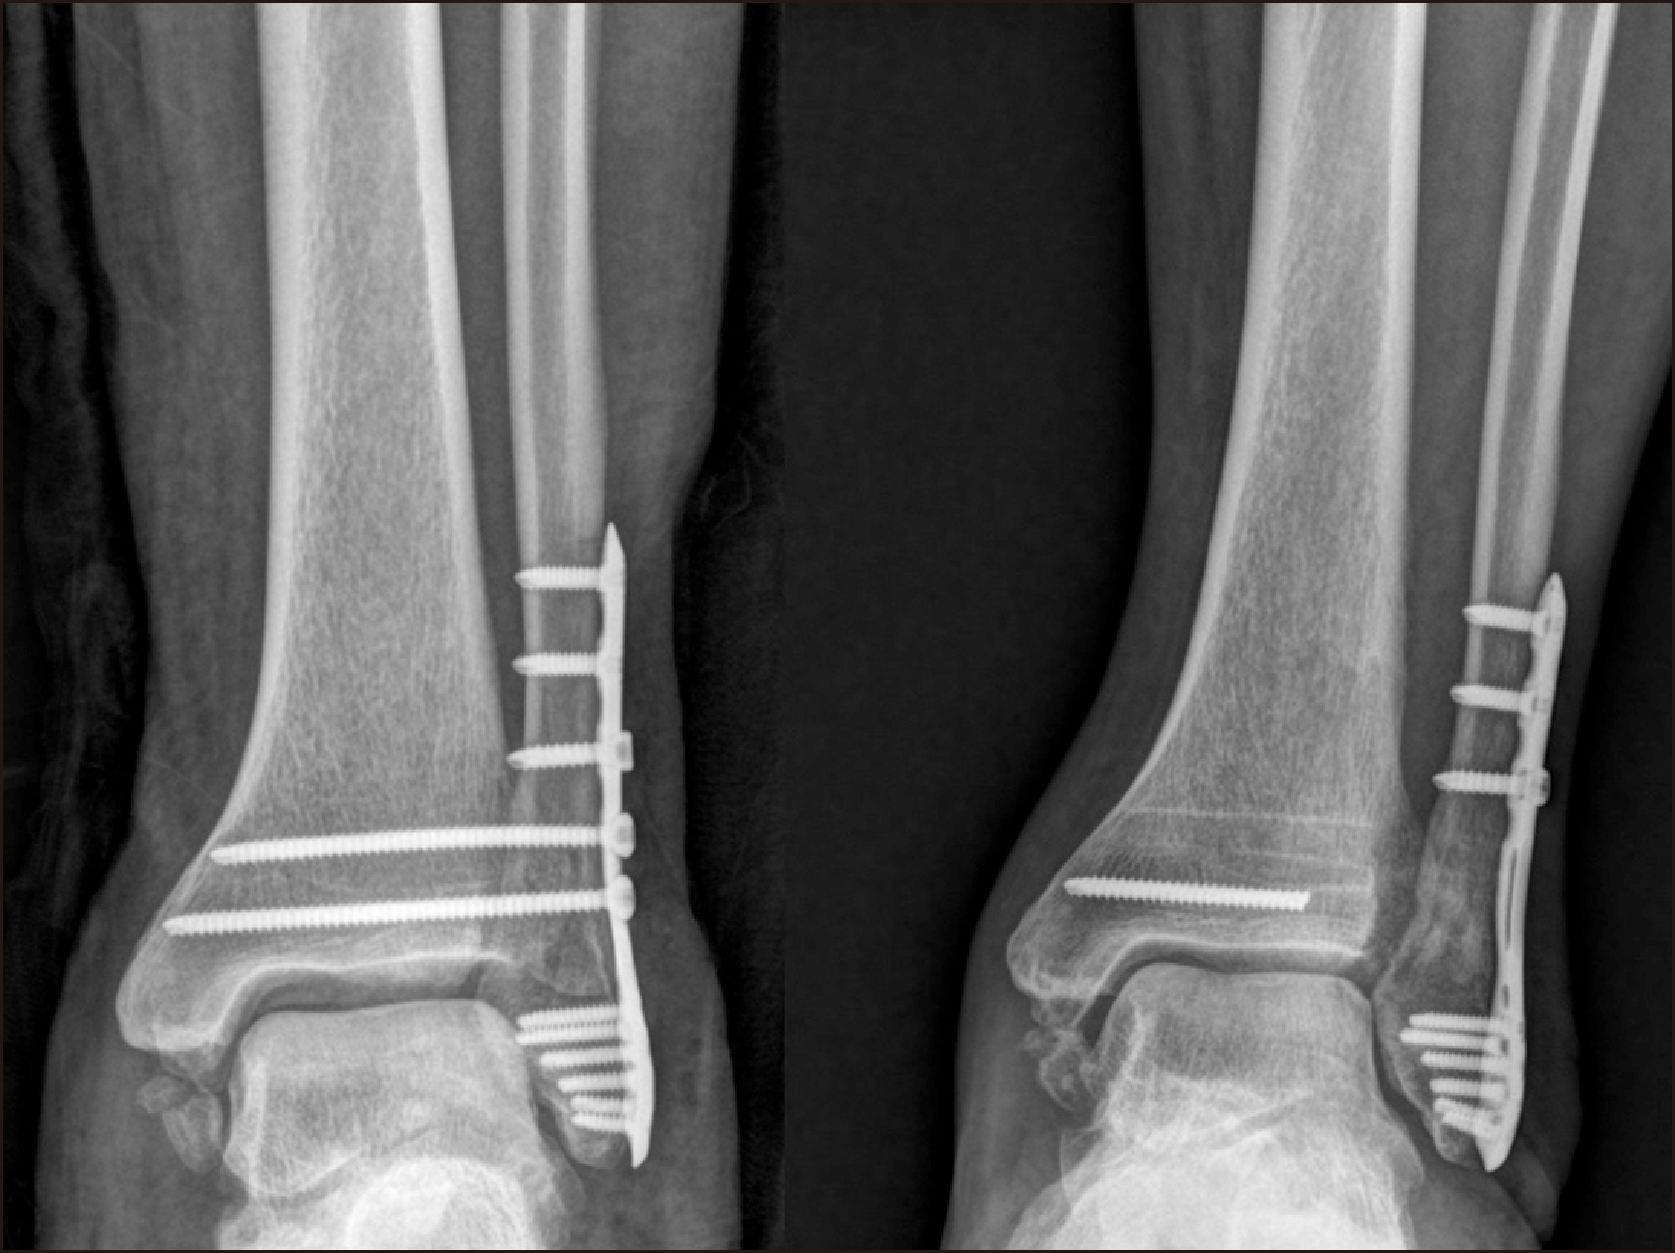

방사선학적 결과상 경비 간격, 경비 겹침, 내측 빈 공간의 측정치는 수술 전, 수술 직후 나사못 고정군과 봉합사 단추 고정군간에 통계학적으로 의미있는 차이가 없었으나 술 후 1년에서는 두 군간에 통계학적으로 의미있는 차이가 있었다(Table 4). 나사못 고정군과 봉합사 단추 고정군에서 수술 전과 수술 후 1년에 측정된 지표는 대응표본 t-test상 유의미한 정복 정도를 보여 나사못 고정 수술이나 봉합사 단추 고정 모두 효과적인 치료인 것으로 나타났다(Table 5). 나사못 고정군과 봉합사 단추 고정군의 수술 직후와 수술 후 1년의 측정된 지표에 대하여 대응표본 t-test를 하였는데 나사못 고정군은 의미있는 차이를 보여 수술 직후 정복된 정도가 1년이 지나자 다소 정복이 느슨해지는 것으로 나타났으며(Fig. 3), 봉합사 단추 고정군은 그 차이가 없어 수술 직후의 정복이 수술 후 1년이 지나도 잘 유지되는 것으로 판단되었다(Table 6).

수술 1년 후에 조사한 AOFAS 점수는 나사못 고정술을 시행한 군에서 86.8점, 봉합사 단추 고정군에서 87.5점이었으며 이는 통계학적으로 유의미한 차이가 아니었다(p=0.728) (Table 7).

경비 결합 나사못을 이용한 고정술과 봉합사 단추를 이용한 고정술을 시행한 환자에서 방사선학적 지표에 대한 연구들은 여러 논문에서 다루어졌다. Laflamme 등7)은 동적 고정이 정적 고정보다 더 나은 방사선학적 결과를 보인다 하였다. Zhang 등5)은 봉합사 단추로 수술한 경우 부정 정복의 위험이 덜하다고 하였다. 본 연구에서는 경비인대 나사못을 이용한 환자군과 봉합사 단추를 이용한 환자군에서 수술 직후 방사선적 지표는 차이가 없었으나 수술 1년 후 방사선학적 지표를 비교하였을 때 봉합사 단추로 치료한 환자군이 수술 직후의 관절 정복된 정도를 수술 1년까지도 변함없이 유지하는 것으로 나타났다. 나사못 고정으로 치료한 환자군은 수술 직후에 얻었던 정복이 수술 1년이 지난 뒤에는 다소 느슨해 지는 것으로 확인되었다. Schepers 등16)은 나사못 제거 후에 6.6%에서 원위경비관절의 재이개가 발생하였음을 보고하면서 나사못을 조기에 제거하는 경우 재이개의 발생이 높아지니 최소 수술 후 8∼12주 후에 제거할 것을 권하였다. 그러나 본 연구에서는 전례에서 12주 이상이 지나서 나사못을 제거하였는데 재이개까지는 아니었지만 원위경비관절이 다소 벌어지는 것으로 나타났다. 이렇게 다소 느슨해지는 현상이 어떤 결과를 초래할지에 대해서는 장기적인 추시가 필요한 부분이나 술 후 1년이 지난 시점에서 AOFAS 점수로 평가한 임상적인 결과는 봉합사 단추 고정군과 차이는 없었다. Jordan 등17)과 Hosin 등18)도 나사못 제거 후 원위경비관절이 벌어지는 것을 보고하였다. 그러나 경미하게 벌어지는 것이 임상 결과에는 영향이 없음을 보고하였는데 본 연구의 결과와 유사한 소견이다. 12주가 인대가 하중을 견딜만큼 견고한 치유를 얻기에 부족한 기간인지 아니면 체중부하를 허락하지 않는 치료법이 인대의 재형성에 좋지 않은 영향을 미치는 것인지는 명확한 판단이 힘들 것으로 보인다.